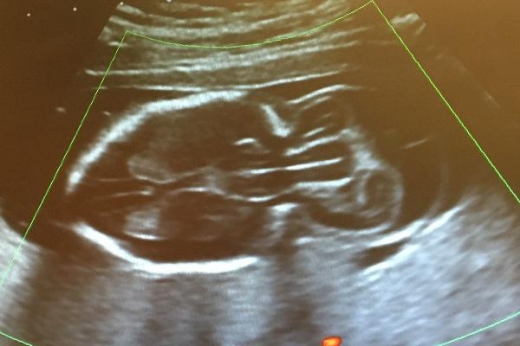

북아일랜드 아마주 출신의 엄마 애널리 기브니(24)는 임신 20주차에 절망적인 소식을 듣게 됐다. 검사 결과 뱃속의 아이에게 ‘뇌류’ 진단이 내려진 것이다. 뇌탈출증이라고도 불리는 이 질환은 뇌가 머리 뒤쪽에서 자루모양으로 돌출해 자라는 상태를 말하는데, 임신 중 아이의 신경관이 완전히 닫히지 못했을 때 일어난다.